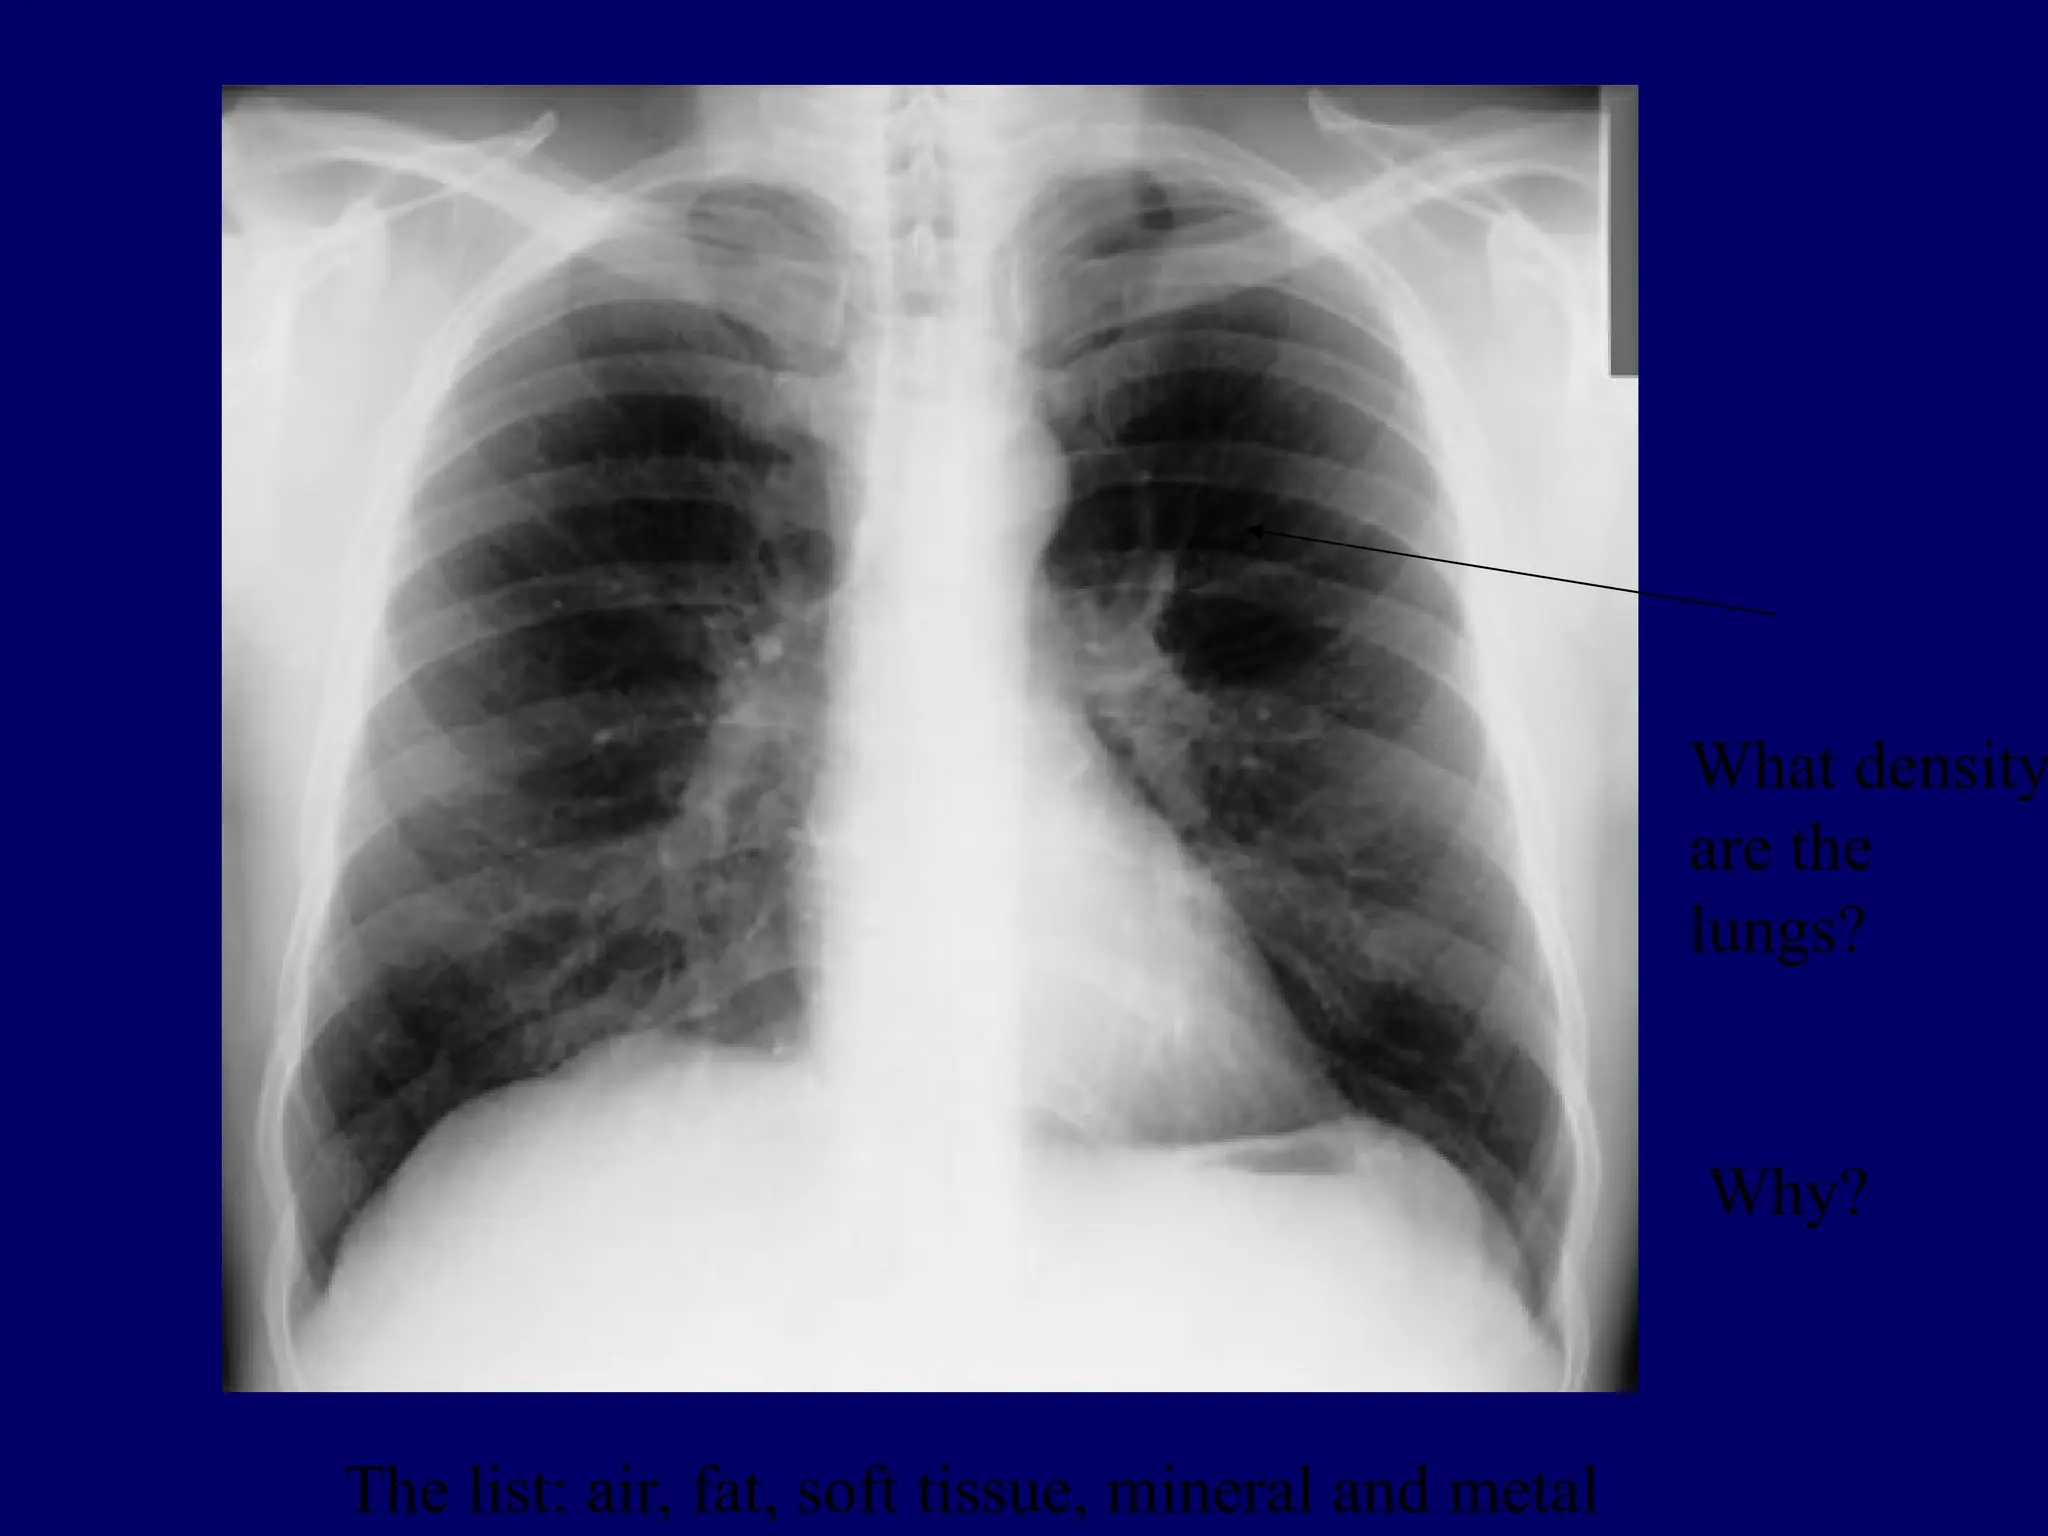

What density

are the

lungs?

Why?

The list: air, fat, soft tissue, mineral and metal

Summary:  X-rays passthrough the body to varying degrees  Higher atomic number structures block x-rays better, example bone.  Lower atomic number structures allow x-rays to pass through, example: air in the lungs. Question: If x-rays were blocked to the same degree by all body structures, could we see the internal parts of the body?

5 basic radiographicdensities from black to bright white  Air  Fat  Soft tissue/fluid  Bone/mineral  Metal

What density are the lungs? Why? Thelist: air, fat, soft tissue, mineral and metal